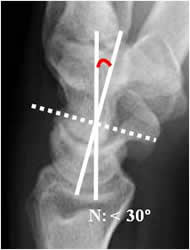

Angulo grandelunado:

Con una amplitud normal entre 0º y 30º. El eje del hueso grande se traza de la parte media de la cabeza, a la parte mas inferior de su superficie articular.

En la inestabilidad tipo DISI (dorsal inestabilidad del segmento intercalado), se aprecia desplazamiento anterior y angulación dorsal del lunado, con aumento de los ángulos escafolunado por desplazamiento anterior del escafoides y del grandelunado por desplazamiento dorsal del lunado (27, 28). (Fig 53 y 54).

Fig 53. Angulo grandelunado.

A: Rx lateral de muñeca. Intersección entre los ejes de los huesos grande y lunado.